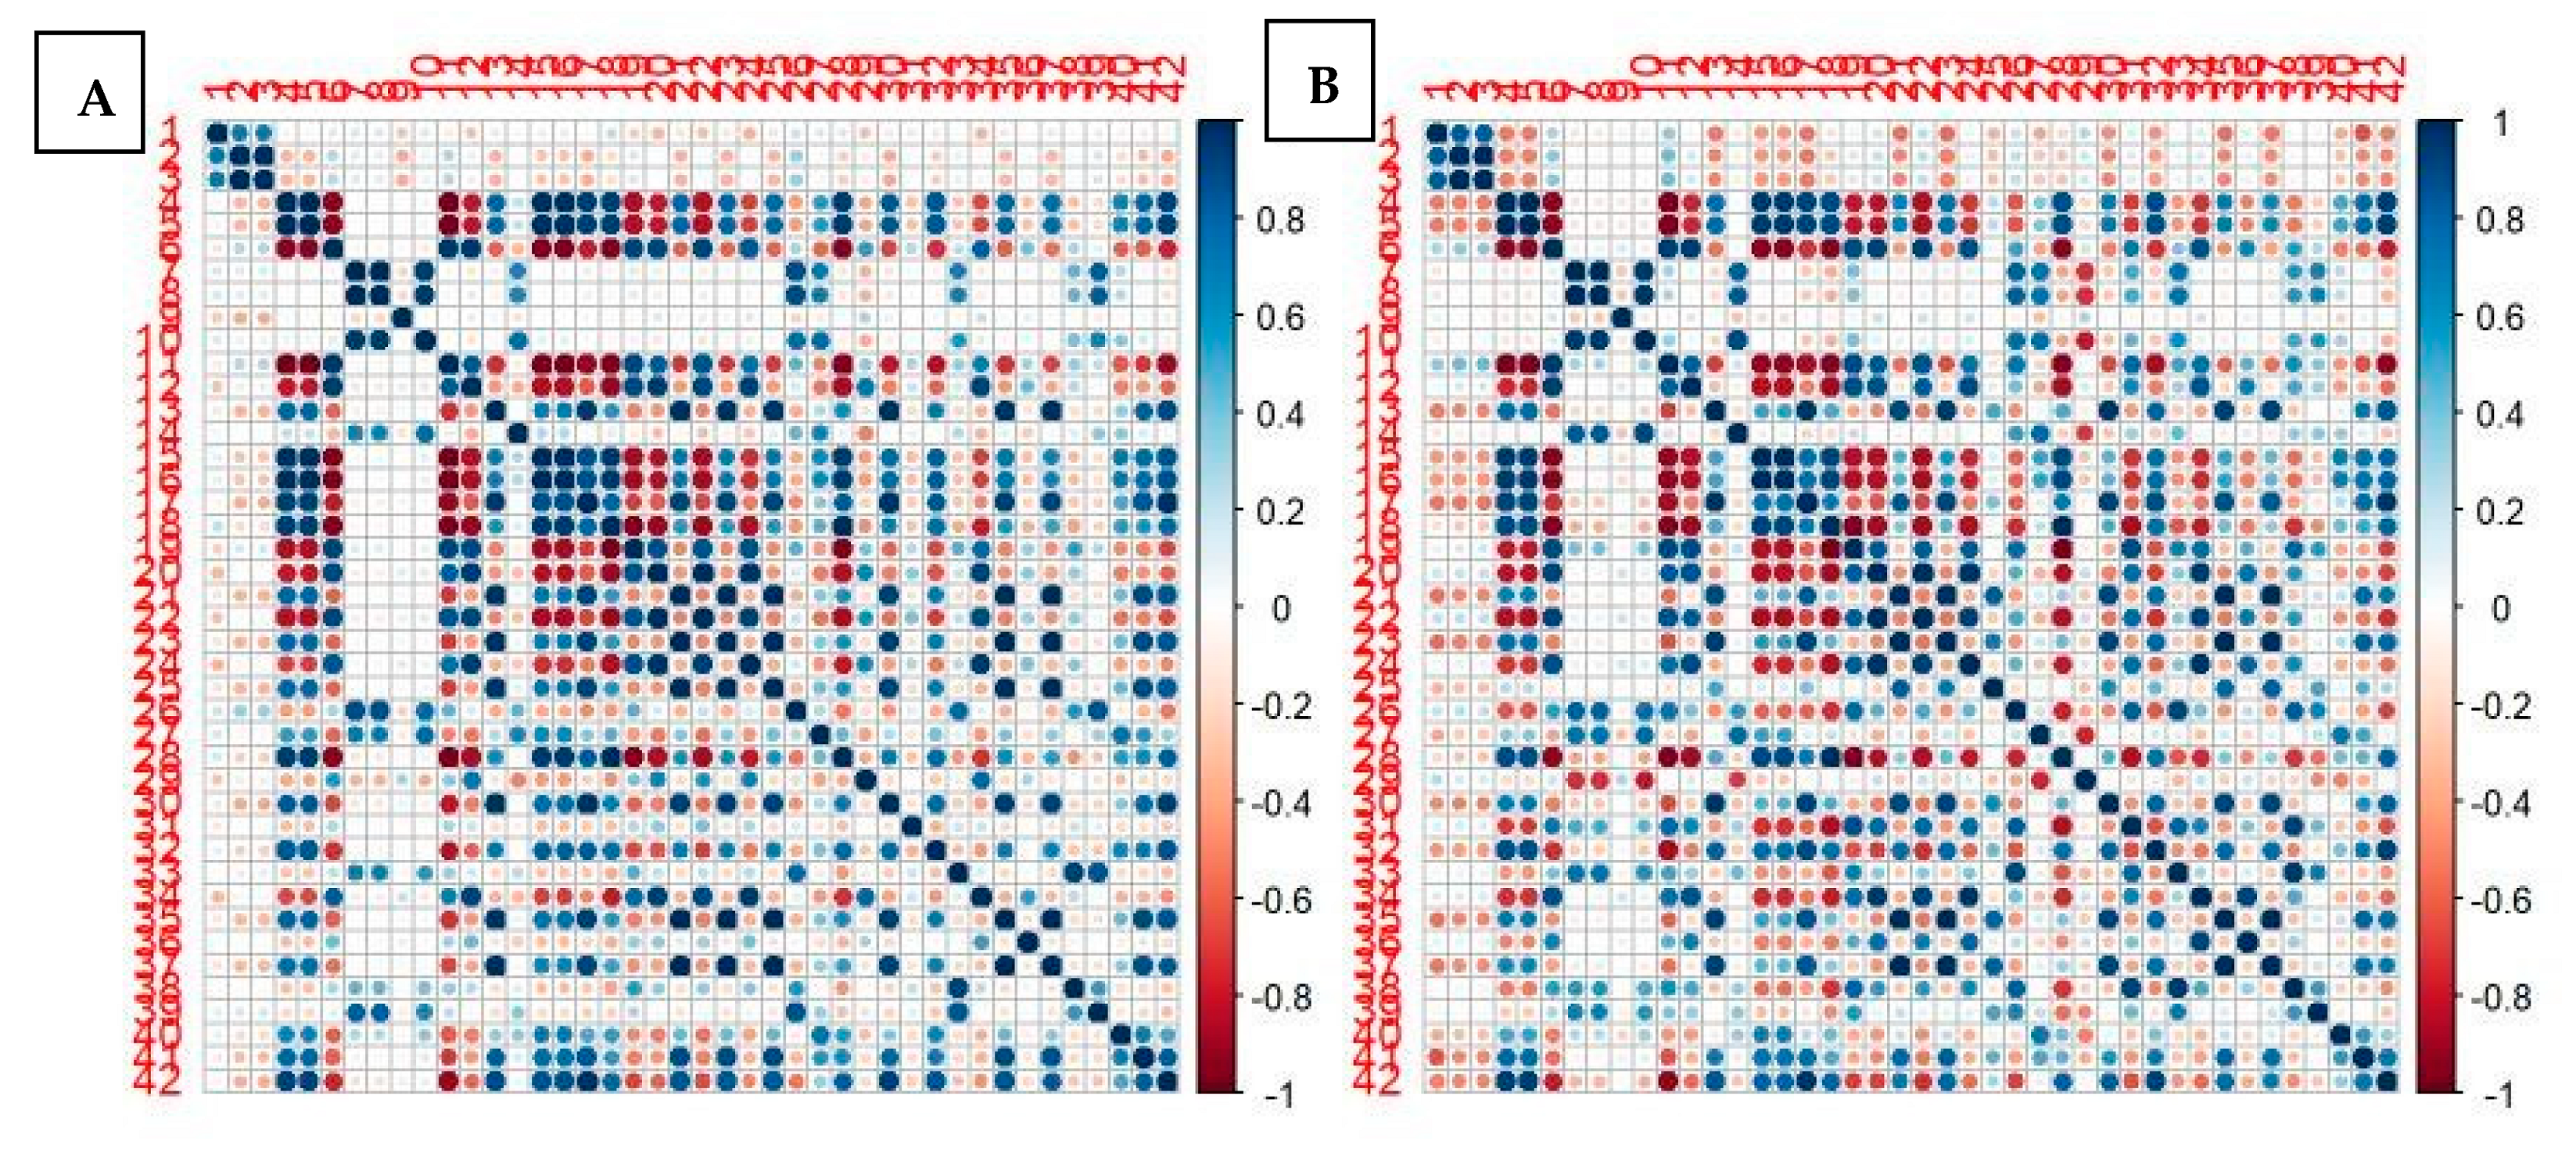

2.4. Statistical Analysis

- Univariate analysis: a univariate analysis was performed on three different sets; the set of patients were treated with Scanner 1, Scanner 2, and the entire dataset. The aim of this step was to figure out how different technologies can affect the relationship between each RF and the clinical outcome.

- Bivariate analysis: with the aim of developing three predictive models (Scanner 1, Scanner 2, and for both the scanners), we analyzed the entire set of the possible couples of variables (the Cartesian product of the radiomics and the main clinical features, such as age, gender, nodule size, side). For each couple of variables, we calculated the bivariate logistic regression model and then we ranked them on the basis of the area under the curve (AUC) under the receiving operator curve (ROC) after a 10-cross fold validation training/testing test.

3.2. Comparison between the Two PET/CT Scanners